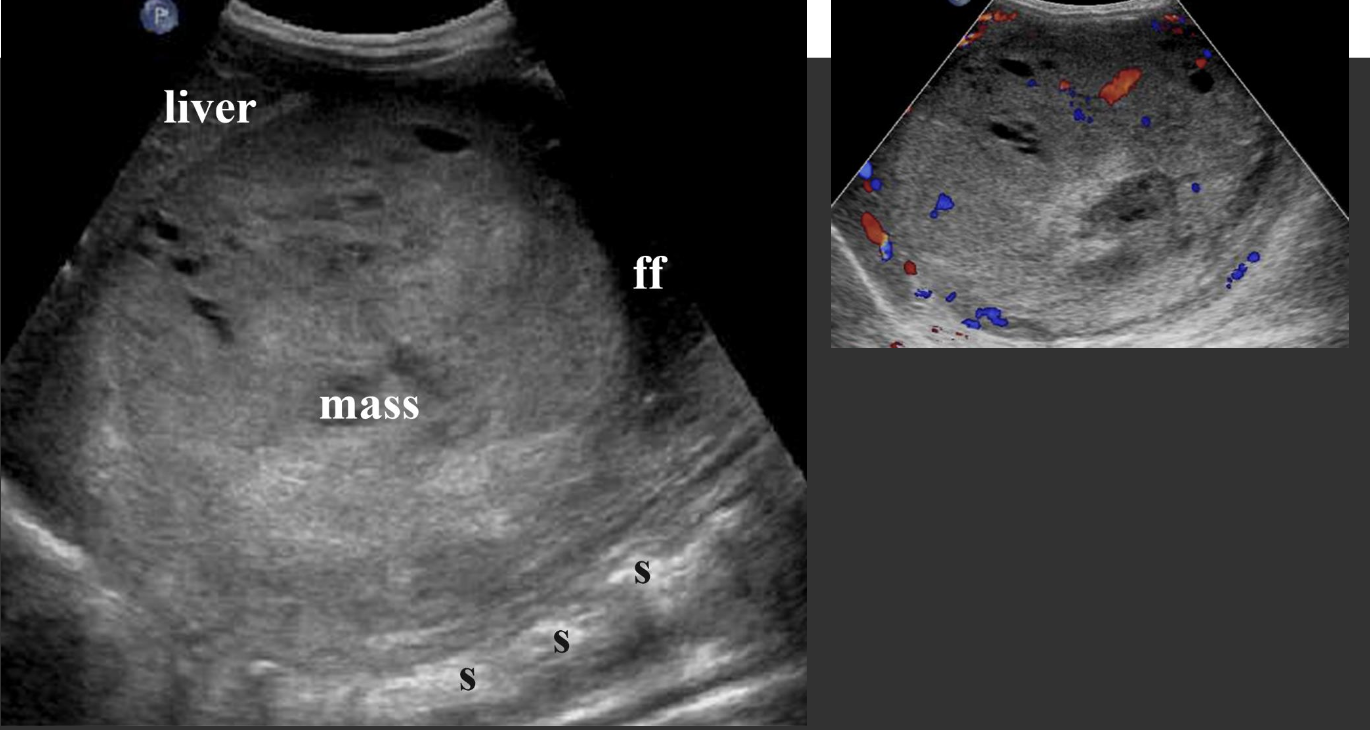

Splenic Trauma → blunt trauma usually resulting in hematoma

clinical hx: usually blunt abdominal trauma, underlying splenomegaly increased risk

s/sx: LUQ pain, low hematocrit from bleeding, abdominal swelling/bloating discomfort

2D US: capsule intact = subcapsular hematoma (conforms to spleen shape), ruptured capsule = free fluid/hematoma may form (check abdominal gutters for free fluid)

color doppler: avascular

DDX: splenic infarction, splenic abscess